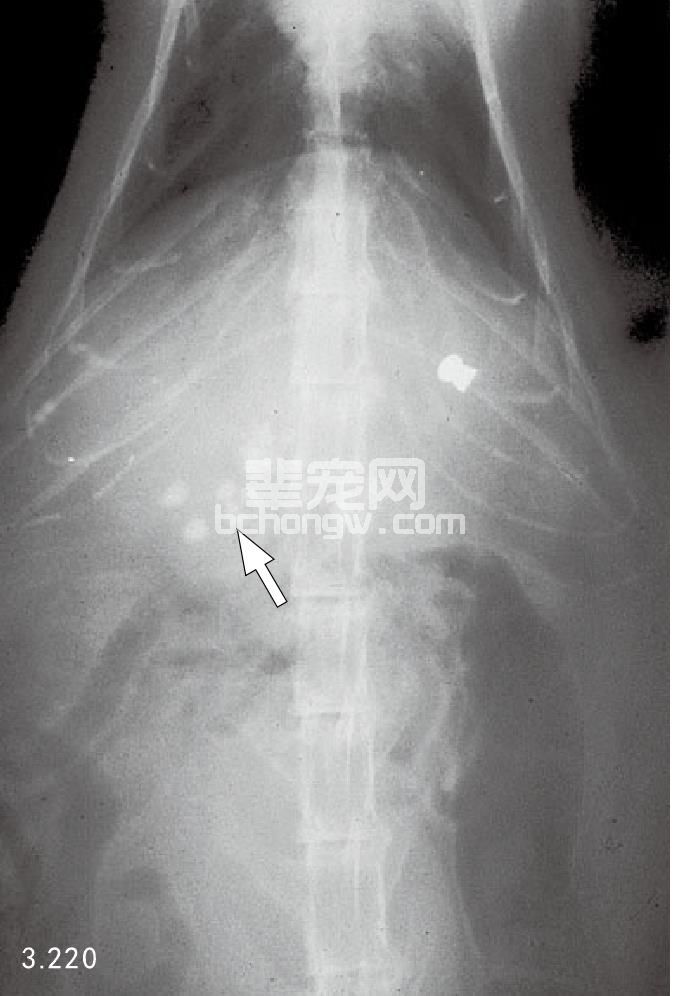

概述 犬和猫胆结石偶见。多数是在腹部X线检查或尸体剖检时偶然发现(图3.220)。肝结石很少能导致总 胆管阻塞,患有肝病的动物X线检查偶然发现结石,但手术去除是不合理的。

图3.220 猫腹部X线片检查发现有一堆胆结石(箭头所指),这是一个偶然 发现(石头像气枪子弹)。

临床症状 胆结石常常不出现临床症状,而是在尸体剖检或X线检查

时偶然发现。如果出现症状,包括呕 吐、黄疸、厌食、发热和腹部不适。